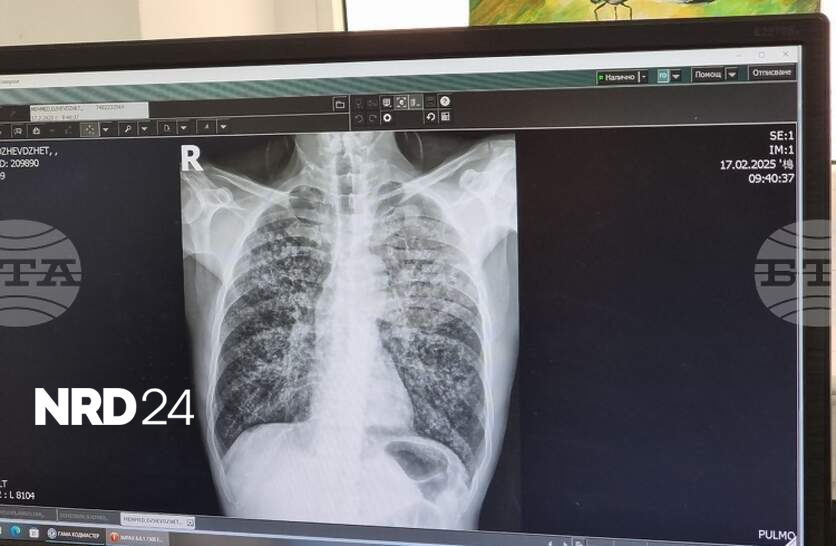

Университетската болница „Д-р Георги Странски“ в Плевен организира кампания за оценка на риска от белодробна туберкулоза, съобщиха от пресцентъра на здравното заведение. В отделението за диспансерно наблюдение на болни с пневмо-фтизиатрични заболявания ще се извършват безплатни прегледи от 23 до 27 март, всеки ден от 12:00 до 14:00 часа. Необходимо е предварително записване на място или на тел. 064/886 650 с цел по-добра организация на работата, допълват от болницата. Отделението вече се намира на нов адрес в Плевен – Втора клинична база, бул. „Владимир Вазов“ № 91. Всички процедури в рамките на кампанията са напълно безплатни за участниците, независимо от здравноосигурителния им статус. Те включват попълване на анкети, медицински прегледи и консултации със специалисти. При наличие на индикации медицинският екип ще извършва и допълнителни изследвания, като проба Манту и рентгенография на белите дробове. Кампанията за оценка на риска от белодробна туберкулоза е ежегодна. Тя се провежда четири пъти годишно – през месеците март, юни, септември и декември. В началото на месеца от болницата проведоха и кампания за безплатни прегледи с акцент върху профилактиката на бъбречни заболявания.